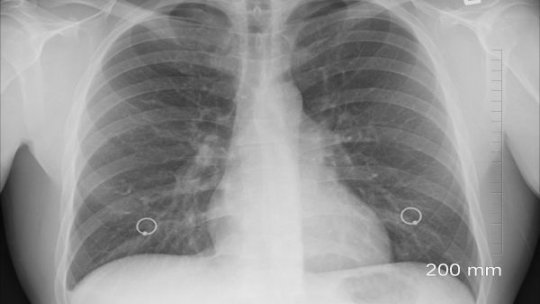

200 de pacienţi cu tuberculoză au fost diagnosticaţi în cadrul unui proiect gratuit de depistare precoce, screening,...